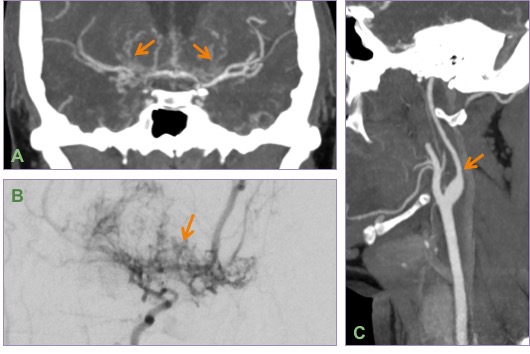

Coronal MIP CT angiogram (A) and right carotid injection DSA (B) showing bilateral severe ICA & MCA narrowing with puff of smoke appearance. Oblique MIP CT angiogram of the neck showing champagne-bottle neck sign seen in advanced cases of Moyamoya disease.

The classic puff-of-smoke appearance of lenticulostriate & thalamostriate collaterals is seen on DSA. Equivalent collateral vessels may be seen on CTA/MRI.

Presence of Champagne bottle neck sign of ICA in the neck suggests a more severe disease and worse prognosis. Please read the AJNR article below for more details.